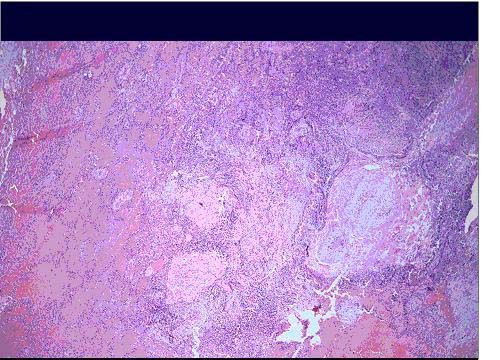

Differential diagnoses considered at this point include: TB, primary lung or metastatic neoplasm, granulomatous lung disease (broad differential), aspergilloma, septic emboli, and other pathogens. Thoracoscopic biopsy for definitive diagnosis is shown (Figures 3,4).

Figure 3

Figure 4

A decision was made to surgically resect the nodule to exclude an early malignant process. The biopsy at low power (Figure 3) demonstrates numerous well-formed granuloma. A high-power view (Figure 4) shows lung tissue with particulate matter (white flecks) deposited within and surrounded by inflammatory cells. Areas of scarring and fibrosis of the interstitium are visible as thick pink areas. Viewed under polarized light, white glowing flecks are visible within the parenchyma, vasculature, and interstitium. These pathological features confirm the diagnosis of pulmonary talcosis. Further clarification of the patient’s drug abuse revealed a history of intravenous injection of opiate tablets.